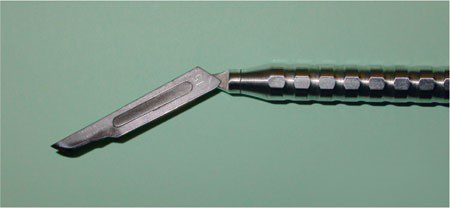

Đường rạch sắc bén là một trong những nguyên tắc quan trọng đối với thao tác phẫu thuật hiện đại. Các dụng cụ và kỹ thuật vi phẫu đã giúp đạt được mục tiêu này ở vùng đòi hỏi kỹ thuật cao như ở viền nướu. Tay cầm tròn, có kết cấu cho phép điều khiển tốt các lưỡi dao vi phẫu bằng tay (hình 2-8).

Hình dạng lưỡi dao truyền thống vẫn giữ một vị trí quan trọng trong phẫu thuật. Đặc biệt, lưỡi dao số 15 được thiết kế để cho phép tiếp xúc tốt với xương và rất có giá trị đối với các đường rạch dọc (hình 2-9).